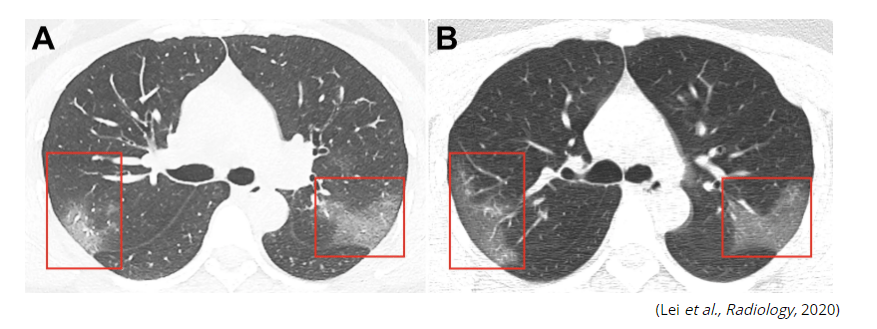

The virus’s displacement of iron from red blood cells aggravates macrophage clustering in the lungs causing the extensive lung damage seen in Covid-patient’s lungs in the CT scan.